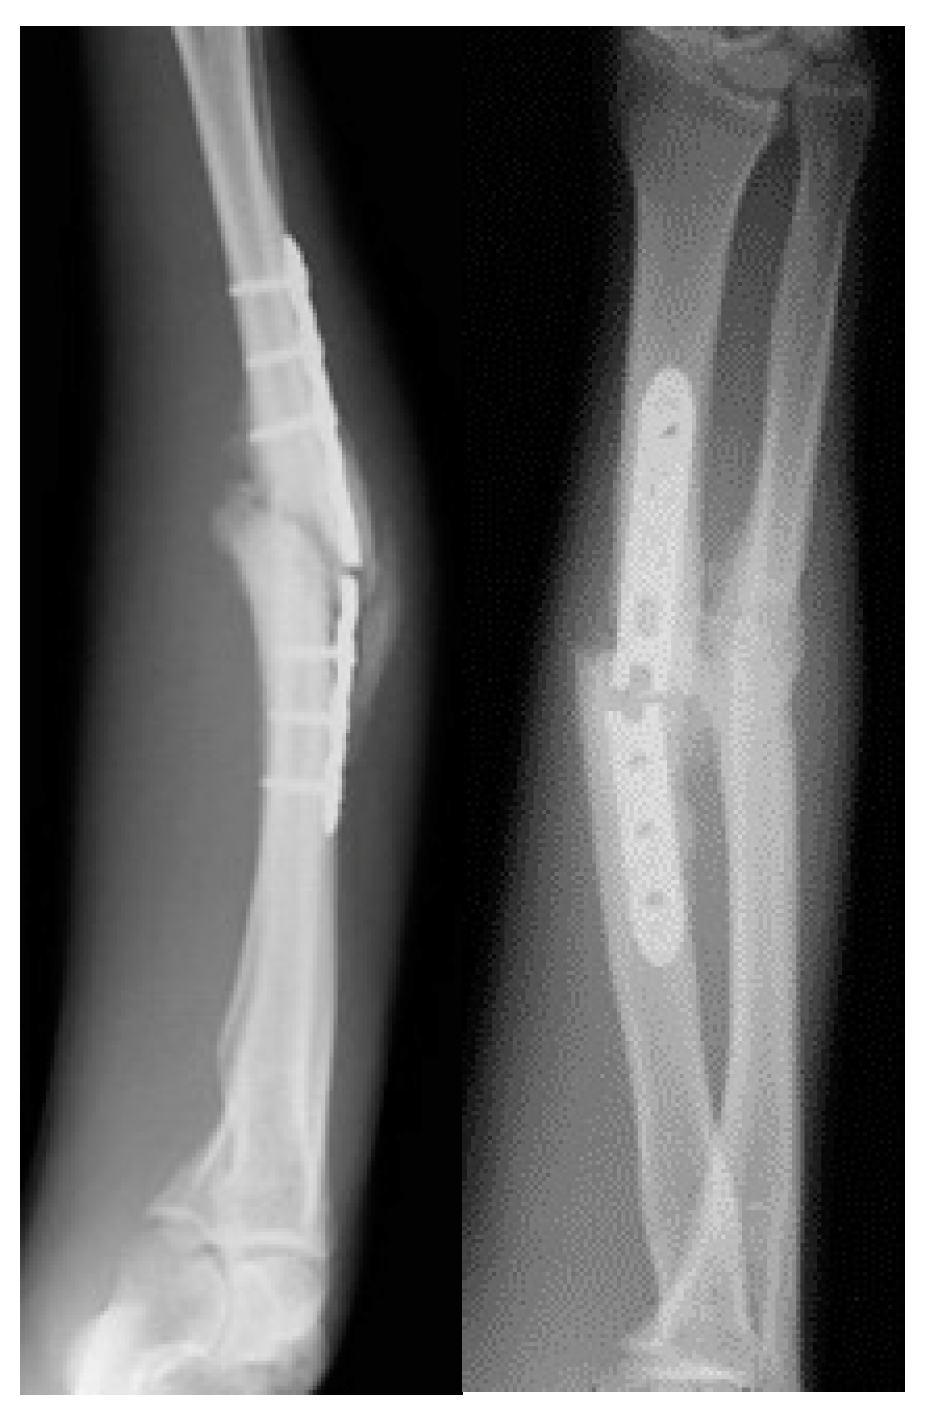

2.1. Risk Factors

2.3. Imaging

2.5. Characterization

4. Adult Forearm Nonunion Surgical Treatment

4.1. Bone Grafting